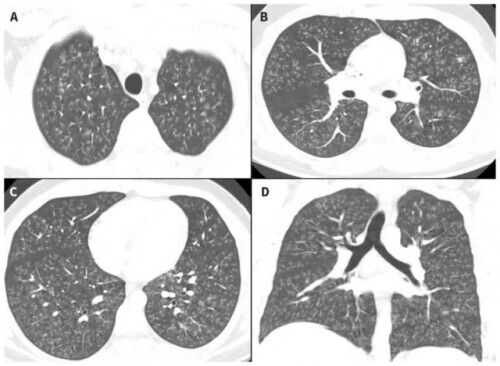

2019年CMAJ报道了一则疑似*子烟电**(含双乙酰)导致的闭塞性细支气管炎案例,患者是一名17岁的加拿大小伙子(CMAJ. 2019, 191, E1321)。据文章描述,这名原本身体健康的小伙子在大量吸食调味*子烟电**和四氢*麻大**酚后出现顽固性咳嗽、进行性呼吸困难等症状,检查后显示发烧、心动过速、低氧血和肺部杂音,结合胸部CT,最后被确诊为急性细支气管炎。

排除了病原体感染的可能后,医生高度怀疑病因和*子烟电**及双乙酰有关。随着病情恶化,这名小伙子甚至用上了ECMO,好在使用大量类固醇激素后病情得以控制。患者住院47天后出院回家,但身体运动能力在几个月内都没有完全恢复。

该名加拿大小伙子入院第一天的胸部CT,他的肺部长满了不正常的、细小的、枝杈般的细纹,这是弥漫性细支气管炎的典型特征图片来源:CMAJ